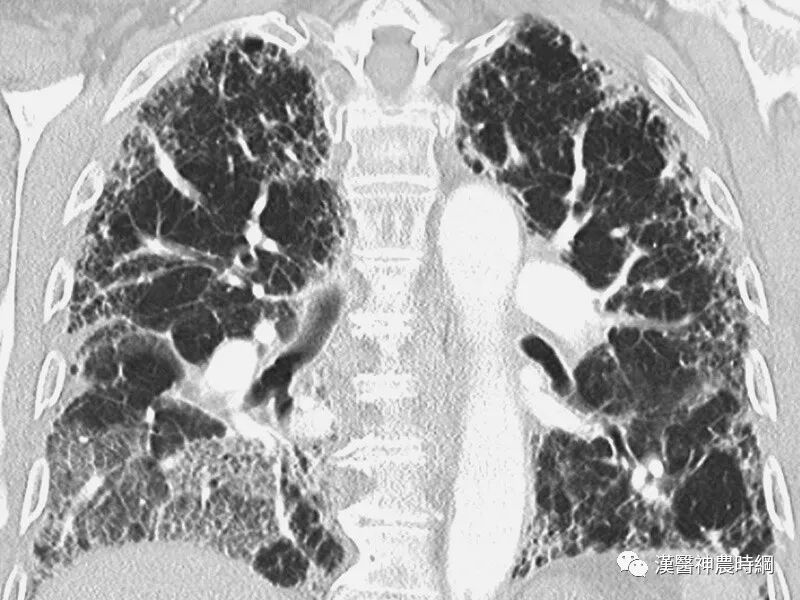

大多数间质性肺疾病都有共同的病理基础过程。初期损伤之后有肺泡炎,随着炎性-免疫反应的进展,肺纤维化泡壁、气道和血管最终都会发生不可逆的肺部瘢痕(纤维化)。炎症和异常修复导致肺间质细胞增殖,产生大量的胶原和细胞外基质。肺组织的正常结构为囊性空腔所替代,这些囊性空腔有增厚的纤维组织所包绕,此为晚期的“蜂窝肺”。肺间质纤维化和“蜂窝肺”的形成,导致肺泡气体-交换单元持久性的丧失。

一般情况下,肺纤维化早期出现肺泡炎,肺泡内有浆液和细胞成分,肺间质内有大量单核细胞,部分淋巴细胞,浆细胞,肺泡巨噬细胞等炎性细胞浸润,肺泡结构完整。进入晚期,慢性炎症已减轻,肺泡结构为坚实的胶原代替,肺泡壁被破坏,形成扩张的蜂窝肺。胶原、细胞外基质、成纤维细胞分布在间质中,肺泡上皮化生为鳞状上皮。基于以上病理变化,临床上多表现为进行性呼吸困难或伴有刺激性干咳,胸部X线显示两中下肺野网状阴影,肺功能为限制性通气功能障碍。病情呈持续性进展,最终因呼吸衰竭而死亡。

早期虽有呼吸困难,但X线胸片可能基本正常;中后期出现两肺中下野弥散性网状或结节状阴影,偶见胸膜腔积液,增厚或钙化。肺组织纤维化的严重后果,导致正常肺组织结构改变,功能丧失。就是大量没有气体交换功能的纤维化组织代替肺泡,导致氧不能进入血液。患者呼吸不畅,缺氧、酸中毒、丧失劳动力、靠呼吸机生存,最后衰竭、死亡。